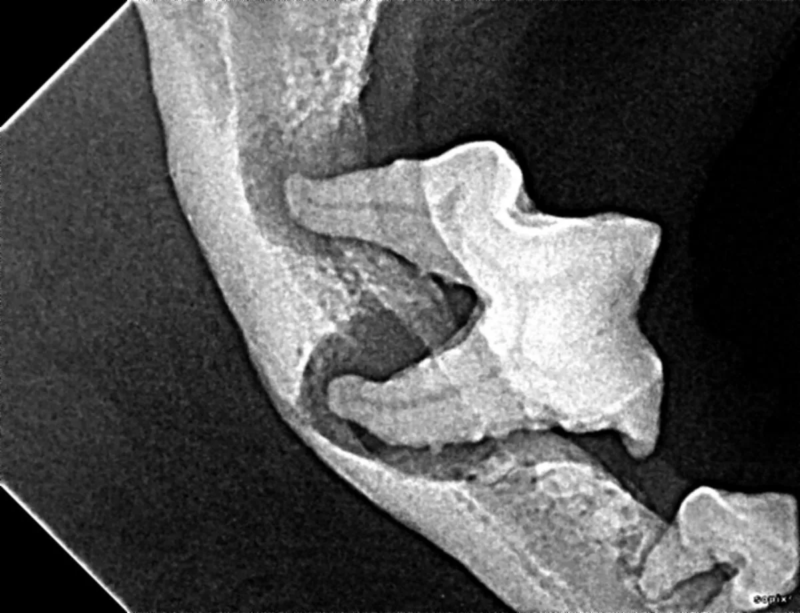

Cone Beam Computed Tomography

The Center now provides advanced imaging via cone beam CT. Cone beam CT is excellent for visualization of bony structures of the skull, nasal cavity, teeth, and ears. Cone beam CT is especially helpful for diagnosing dental disease and evaluation of jaw fractures. It can also be useful for evaluating the sinuses and tympanic bulla. Cone beam CT can be used in conjunction with nasal biopsy and culture to evaluate nasal discharge whether chronic or acute.

Repair of Maxillofacial Fracture

Pets can be involved in trauma that can cause fractures to their head, teeth, and jaw bones. Correctly repairing these fractures is extremely important for your pet to have normal function of their mouth. If a jaw fracture is allowed to heal in an abnormal position, your pet may have great difficulty chewing and can be in significant pain. Many fractures can be successfully treated with minimally invasive oral procedures, but more complicated cases may require bone plating techniques. The Center offers cone beam CT imaging which provides extremely detailed images of the bones of the head and skull. Advanced imaging with CBCT facilitates selection of the best surgical technique to get your pet back to eating and comfort as soon as possible.